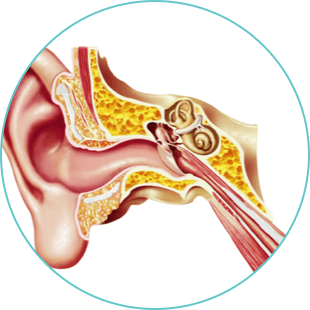

Ears

Lorem ipsum dolor sit amet, consectetur adipiscing elit. Etiam nec aliquam ex, eget consequat est.

- Morbi venenatis non lectus sit amet tincidunt

- Gellentesque sit amet eleifend velit

- Vestibulum fermentum cursus facilisis

- Etiam nec aliquam ex, eget consequat est.

Lorem ipsum dolor sit amet, consectetur adipiscing elit. Ut quis libero eros. Vestibulum fermentum cursus facilisis. Pellentesque sit amet eleifend velit. Donec consectetur posuere tortor a finibus.